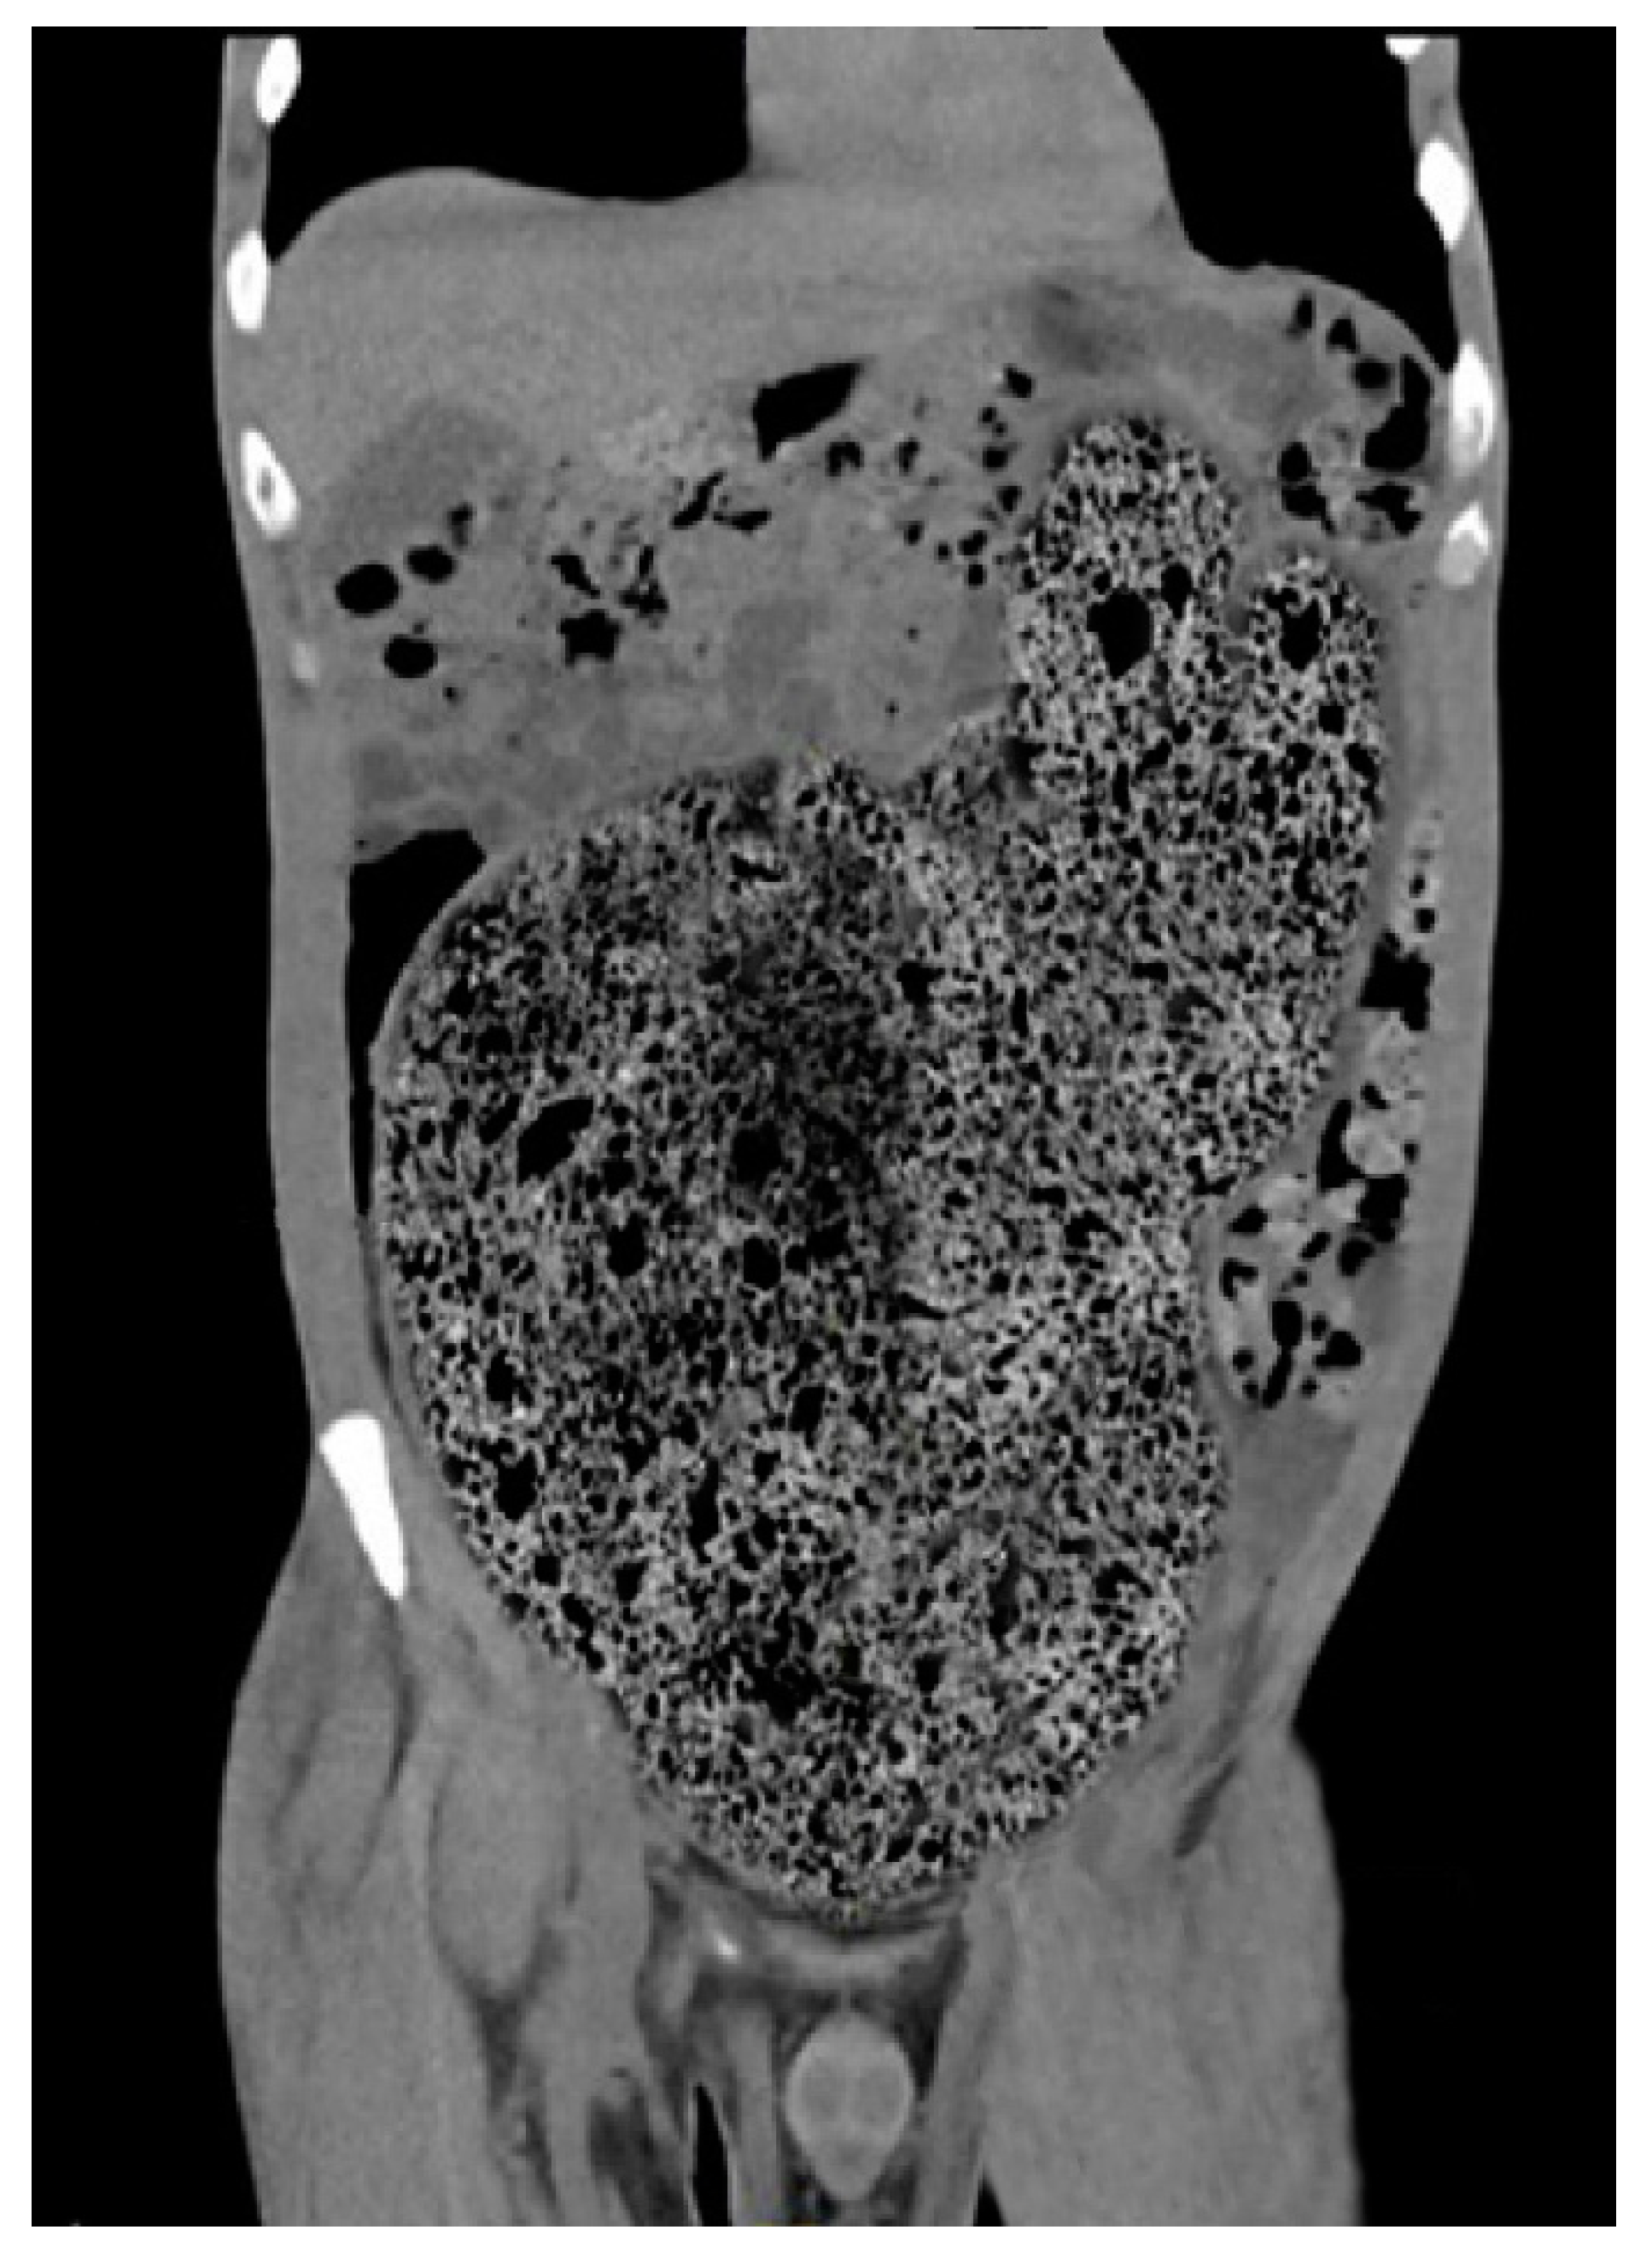

4. Diagnostic Criteria for the Acquired Megacolon